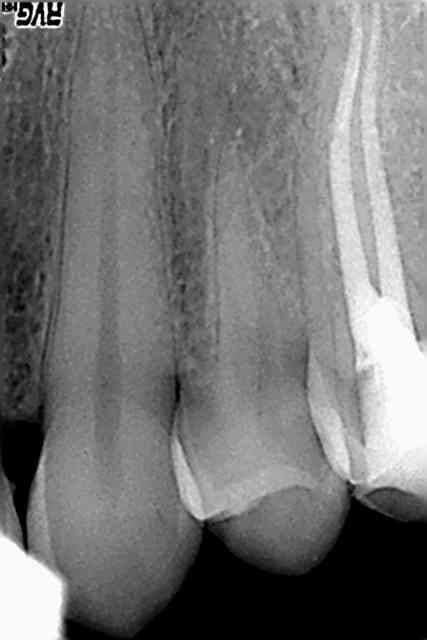

Bon je sais pas comment vous faites. J'ai fait ça ce matin, au protaper, sans mettre très longtemps, sur le contre angle endo, sans rien de spécial dans ma séquence. Et je casse pas. Et j'ai pas de déplacement de canal. Bref je suis entièrement satisfait des protapers.

Edit : 2eme radio sans l'apex, la dent est très longue j'ai eu du mal à viser (26mm). Obturation mixte : fouloir + thermomécanique au mac spadden.

Concernant la première, est ce que ton dernier instrument a été jusqu'à l'apex, ou bien s'est il arrêté juste avant la courbure finale (très serrée).Et ce que l'on observe à la radio serai simplement la fusée de l'obturation qui suivrai le cathétérisme ?

Je me le demande aussi, je suis presque sur d'avoir cathétérisé à 0,5mm de l'apex (localisateur + digue) et par la suite j'ai amené tous mes instruments à cette LT (simplement S1, S2, F1, F2, pas de SX/endoflare, pas d'US pas de gates). Bon j'ai jeté les instruments après usage :).

Par contre pas de radio entre préop et obturation, la patiente avait juste RDV pour une "douleur au froid". On comprend pourquoi.

Maintenant le gutta condensor 35/10ème sur 20 mm ça pousse fort en effet...peut être que les instruments n'ont pas vraiment pénétré le crochet. C'est peut être aussi la limite de la zone "tassée" qu'on voit, les fouloirs et condensors sont droits contrairement aux protapers.

J'ai eu la surprise sur la radio finale, je n'avais pas vu ce crochet sur la préop.

et par contre c'est la même 25, qui a bien 2 canaux (radios + ou - angulées)